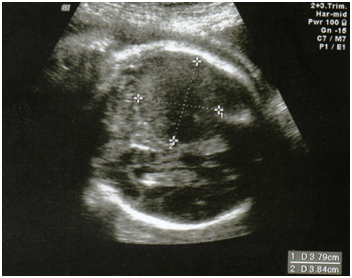

Following referral to our unit, ultrasound showed the head circumference (HC) and abdominal circumference (AC) to be on the 5th percentile. A 4cm homogeneous hypoechoic area was seen in the posterior brain (Figure 1). Differential diagnosis included an infarct, haemorrhage or SOL. MCA PI was markedly low at 0.6, but umbilical artery pulsatile index (UA PI) and ductus venosus pulsatile index (DV PI) were within normal limits. Antiplatelet antibody (anti-heparin PF4), lupus anticoagulant and anti-cardiolipin IgM and IgG antibody were not detected. A repeat ultrasound 2 days later showed similar findings.

Figure 1 Antenatal ultrasound in transverse plane showing a 4 cm homogenous hypoechoic area in right posterior brain.